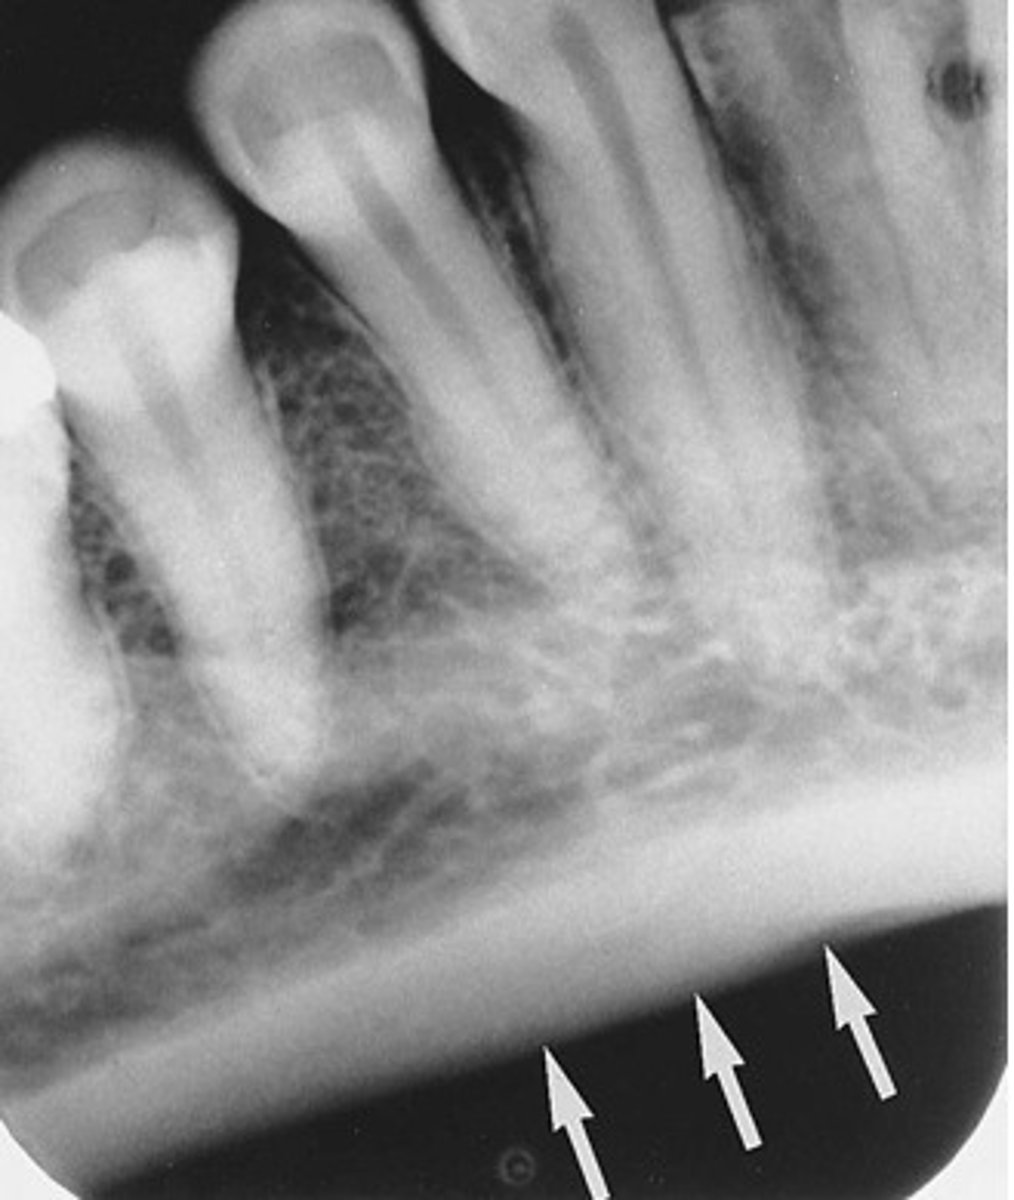

what are the landmarks seen in radiographs of the mandible (change maybe)

external oblique ridge, internal oblique ridge, submandibular fossa, mand canal, mental foramen, genial tubercles, lingual foramen

where can you see the mylohyoid ridge in a radiograph

posterior molar region at apices

where can you see the external oblique ridge in a radiograph

posterior mand molars

where can you see the internal oblique ridge in a radiograph

apicies of molars, inferior to external oblique ridge

where can you see the submandibular fossa in a radiograph

apices of molar teeth, inferior to interal oblique ridge

where can you see the mandibular canal in a radiograph

apcies of molars

does the enternal oblique ridge appear radiopague or radiolucent in a radiograph

radiopaque

does the the submandibular fossa appear radiopaque or radiolucnet in a radiograph

radiolucent

does the mandibular canal appear radiopque or radiolucent in a radiorgraoh